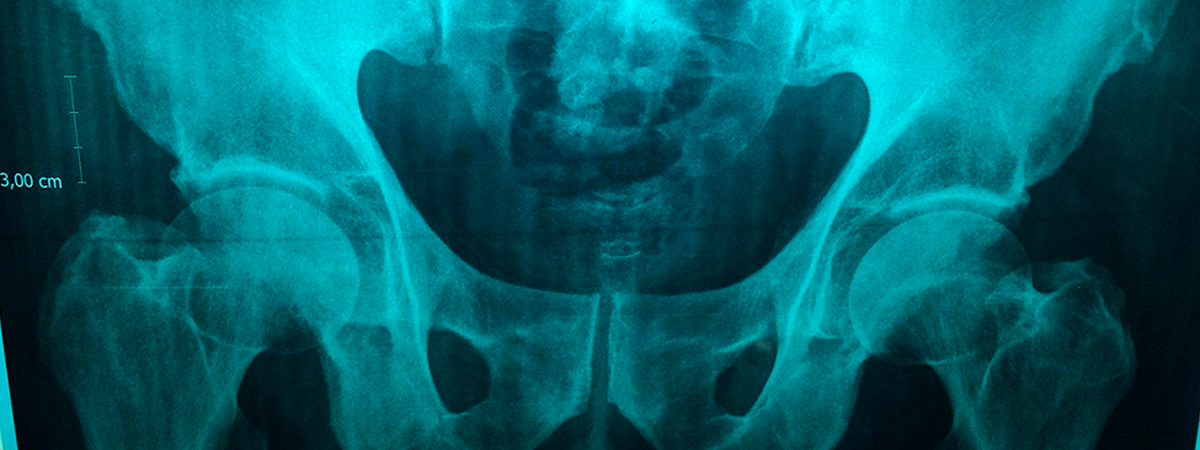

La ocurrencia de una fractura osteoporótica mayor (FOM) conlleva una pérdida de calidad de vida y un mayor riesgo de mortalidad. Diversas herramientas permiten evaluar el riesgo de FOM, y los avances en inteligencia artificial (IA) podrían contribuir a mejorarlas. En este sentido, los algoritmos de potenciación de gradiente (gradient boosting) permiten el modelado de datos no lineal, lo que resulta conveniente para analizar datos complejos como los de los registros médicos.

Según los resultados publicados en Archives of Osteoporosis, en el año índice (2022) el 1,3% de las mujeres sufrieron una FOM, que en el 23,1% de los casos fue una fractura de cadera. El 0,6% de los hombres sufrió una FOM en el mismo período, con un 34,2% de fracturas de cadera.